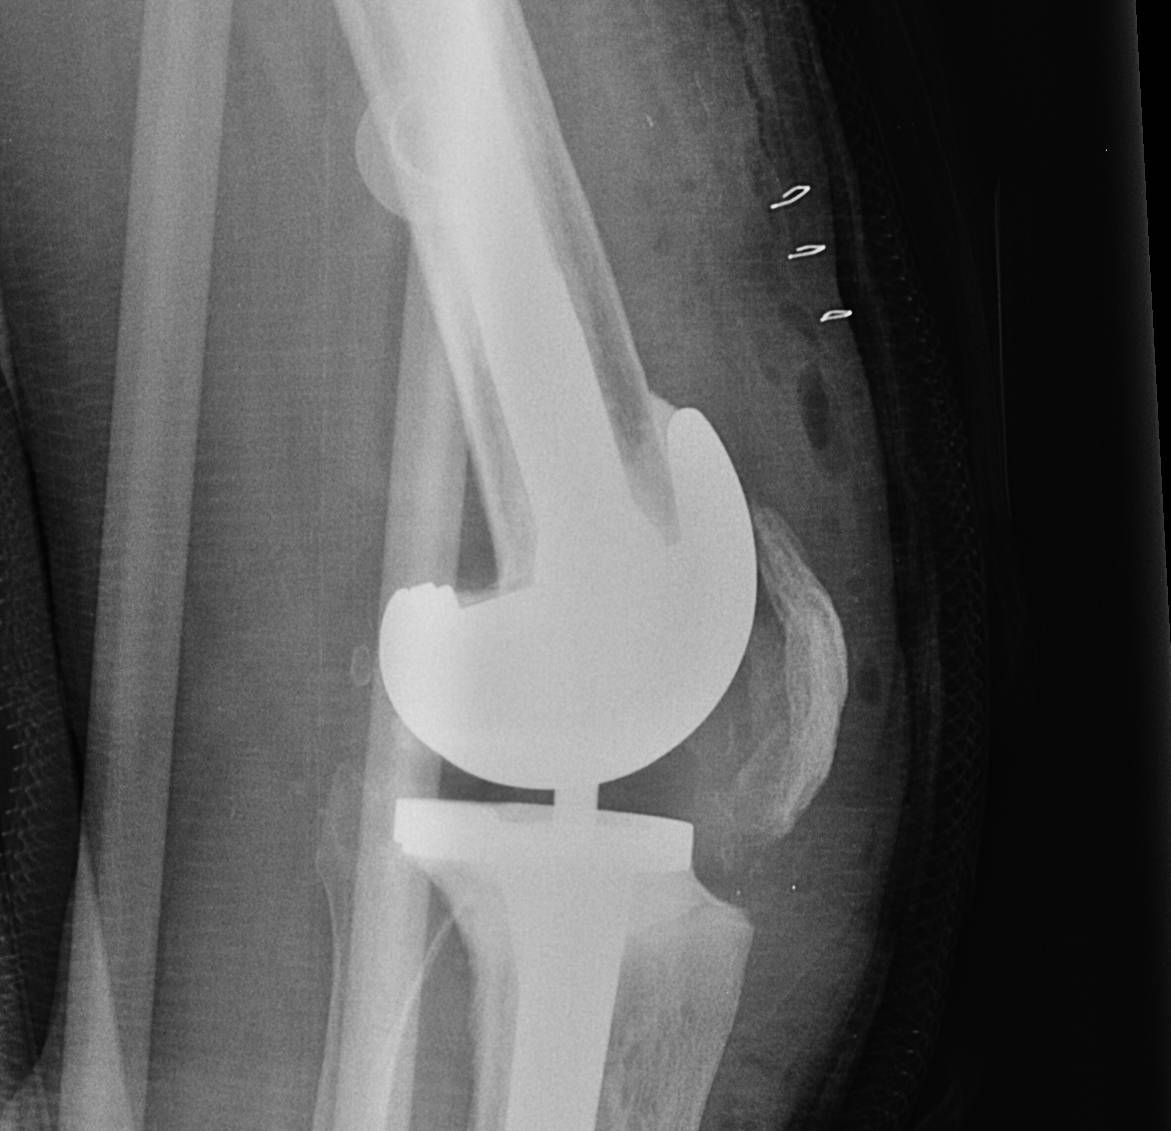

Prepare Femur

Insert trial intramedullary stem

Find IM canal

- entry point important

- if too posterior will flex femur

- if too anterior will extend femur

Ream until press fit

- insert desired length of stem

Distal femoral Cut

Distal cutting block on stem

- want to freshen surfaces minimally

- 1-2 mm off distal surface only

- consider distal femoral augments

- wait to trial extension gap to decide distal femoral augments

AP sizing

Posterior femoral condyles frequently deficient

- require augment posteriorly

- use anatomically sized femoral component

- template from other knee or use previous size from primary

- add augments posteriorly as

May need offset so femoral component sits on IM stem

Rotation

Trans-epicondylar axis most reliable

- posterior femoral condyles may be more deficient laterally than medially

- set correct rotation

- freshen AP and chamfer cuts